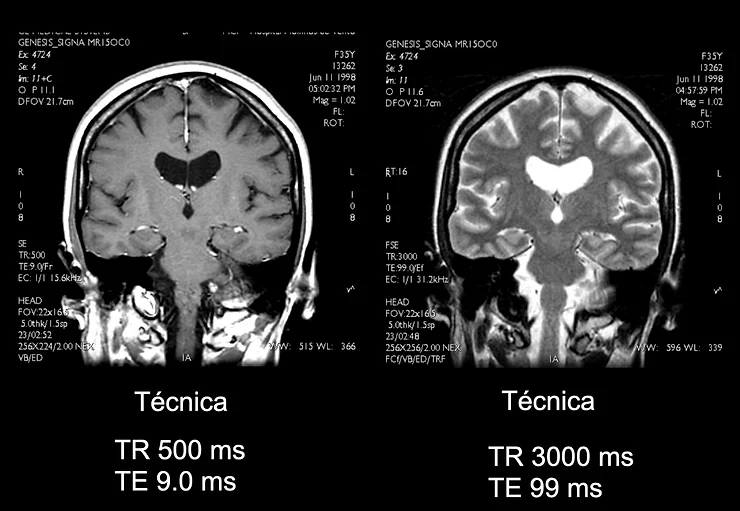

Fig. 1 - Os parâmetros TR e TE são trabalhados em conjunto.

- TR curto e um TE curto produzem uma imagem ponderada em T1 (Ex. TR = 500 ms e TE = 10ms), ou seja, mostra melhor as diferenças de relaxação T1 entre os tecidos;

- TR longo e um TE longo produzem uma imagem ponderada em T2, ou seja, é a informação da diferença na relaxação T2 que mais influenciará a geração de sinal na bobina.

Nesta faixa de valores - 400 a 500 - o contraste entre os tecidos mencionados acima é muito bom, resultando em imagens ponderadas em T1 SE ou FSE de ótima qualidade em relação ao contraste. Lembrando que é preciso que, nestes casos, o tempo de eco (TE) seja o mais baixo possível (TE mínimo), pois com isso não haverá ou será mínima a participação do processo de relaxação transversal desses tecidos no sinal coletado para gerar as imagens. Portanto, não podemos dizer que isso se aplica a todos os protocolos, pois em outras sequências de pulso como as Gradiente Eco ou mesmo as com uso de pulso de inversão (FLAIR, STIR etc), essas relações de contraste se modificam devido a outros parâmetros envolvidos e forma de aplicação dos pulsos de RF e gradientes de campo magnético associados.